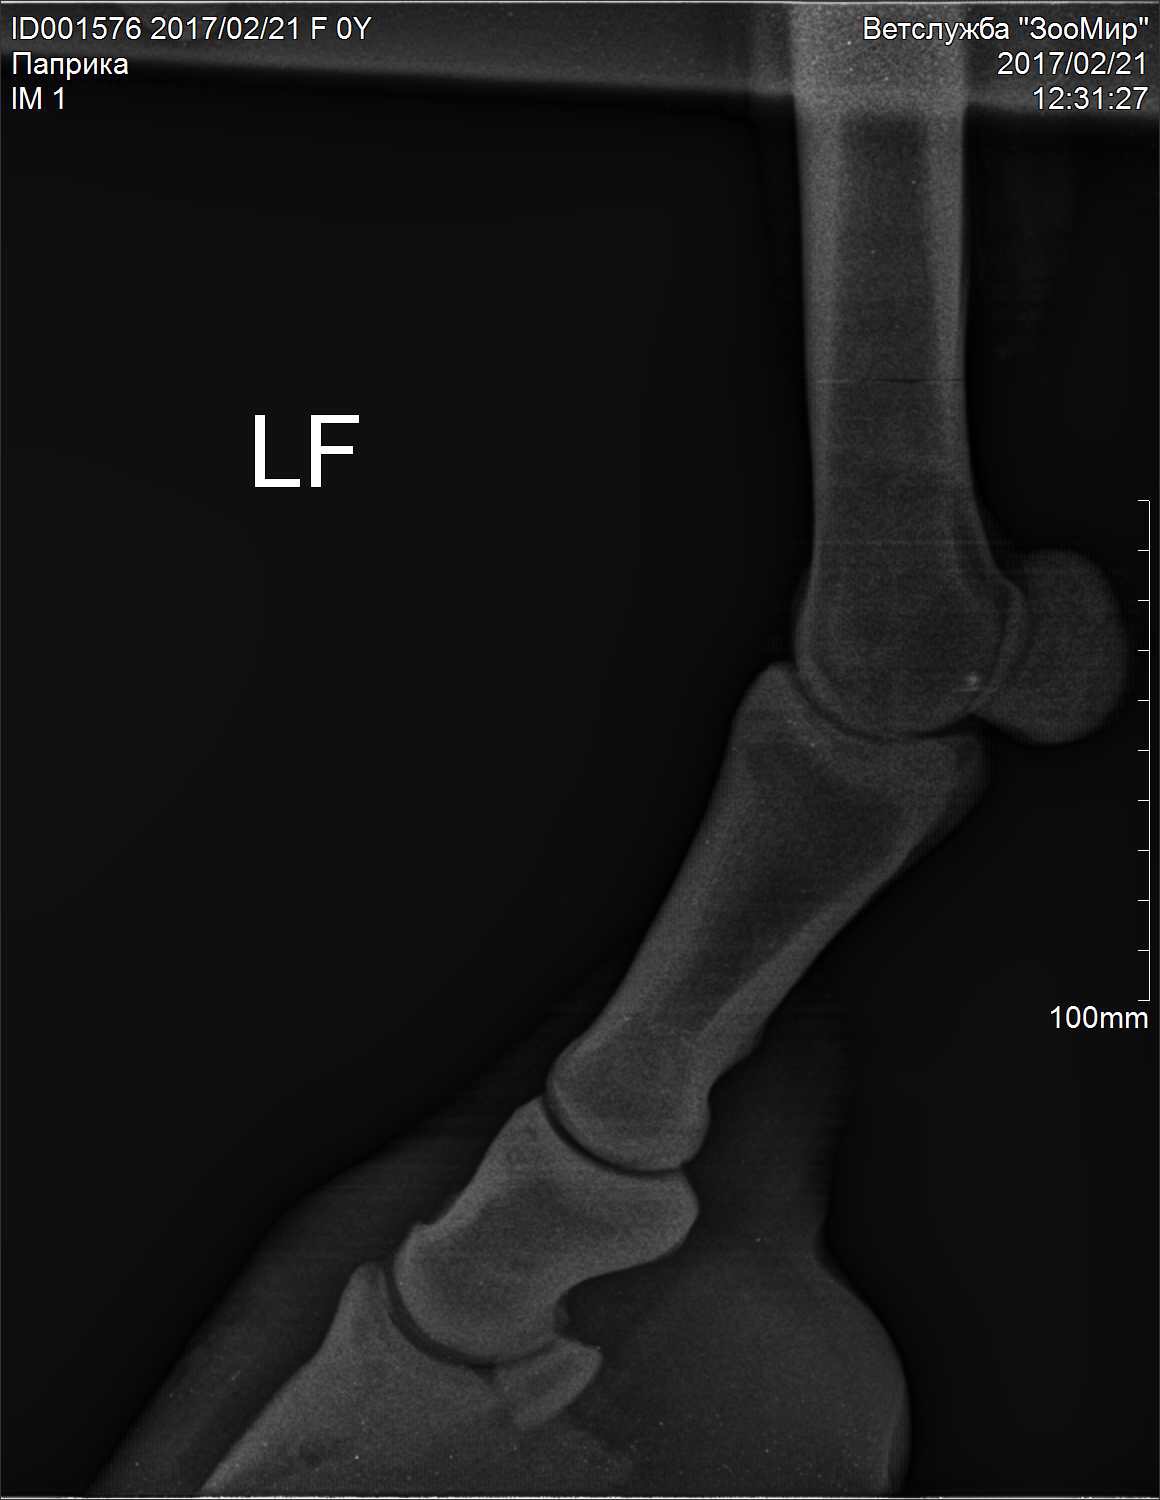

Добрый вечер!!! Помогите пожалуйста разобраться с такой ситуацией: моя лошадь стала хромать на переднюю правую ногу, лошади в мае будет 4 года, заезжена недавно. Работала 2 раза в неделю на корде, один раз верхом. Выгул ежедневный сено вдоволь, овёс пол ковша. Меня это забеспокоило и я вызвала рентген. Врач по снимкам мне сказал, что у нас киста в ПЛ ноге в челночной кости и синдром целующихся позвонков. Из лечения сказал ковать на круглые подковы, 5 фильц, поднимать пятку (лошадь не ковалась). Если подкованная будет хромать, колоть Бонефос. Лошадь молодая и с характером, блокады сделать было невозможно, выдирает ноги. Рентгенили тоже под седацией, но ноги все равно выдирала. Другой врач сказала что у нас перелом мякишного хряща, кисту не наблюдает. Я в панике! ((( Пожалуйста посмотрите снимки, все ли так серьезно?